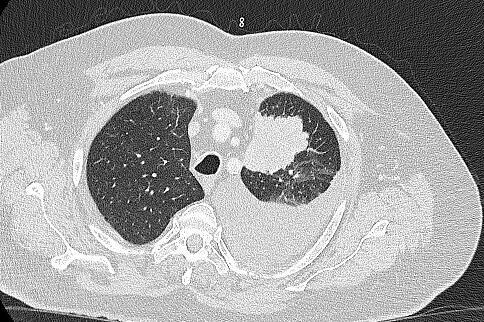

Lungentumor mit Pleuraerguss.